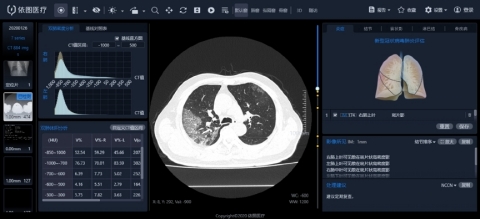

El artículo anunciaba los últimos resultados de su uso de la tecnología de inteligencia artificial para ayudar a los médicos a llevar a cabo un análisis cuantitativo inteligente y la evaluación de los efectos terapéuticos de las nuevas lesiones por coronavirus en base a imágenes de TAC.